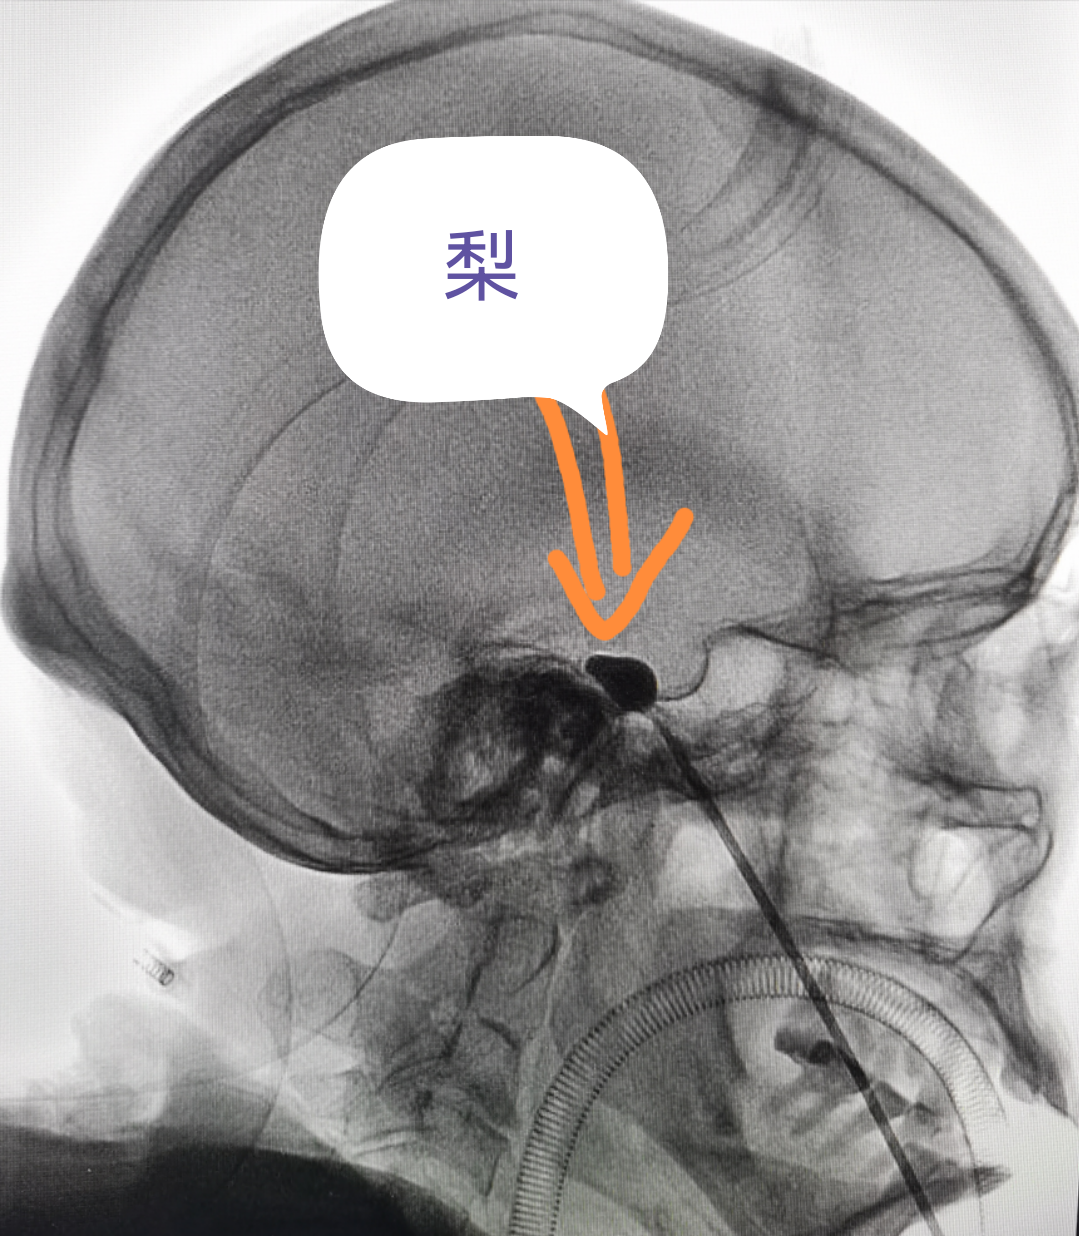

看到這個(gè)“梨”,你會想到什么?

治療三叉神經(jīng)痛中微創(chuàng)技術(shù)在影像上的呈現(xiàn)挺像噠

(看著像梨,哈哈...)

經(jīng)過面部口角處穿刺到三叉神經(jīng)半月節(jié)內(nèi),放入球囊,向球囊里打入對比劑,使球囊擴(kuò)張,完美顯示一個(gè)“梨”形,壓迫3-5分鐘,壓迫毀損感覺神經(jīng),保留運(yùn)動神經(jīng),阻斷疼痛信號傳導(dǎo),達(dá)到止痛目的。適合單支或多支發(fā)病患者,尤其高齡、合并癥多,不愿意接受開顱手術(shù)患者。術(shù)后面部稍有麻木。